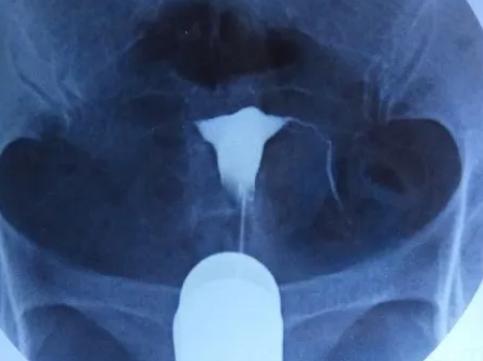

我是一位30岁,患有不孕症的女性,我想要做输卵管造影,请问在做输卵管造影之前我需要准备些什么?精选回答:

做输卵管造影之前需要做的准备,主要是医疗及心理准备。患者首先需要准备好自己的身体状况,避免身体出现不适,以免影响做输卵管造影的效果。其次还需要做心理准备,让自己心情轻松,以便更好地配合医生检查。